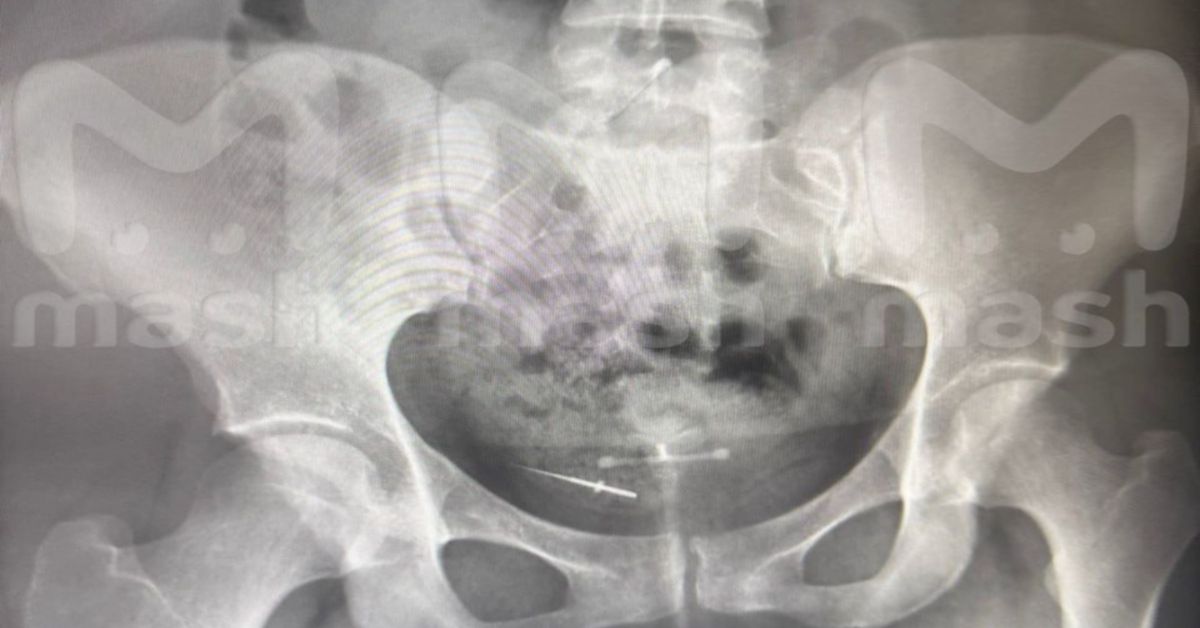

Ой, что это?! Стоматологический инструмент в кишечнике девушки из Башкирии

Как он туда попал? Ни стоматолог, ни сама пациентка не помнят...